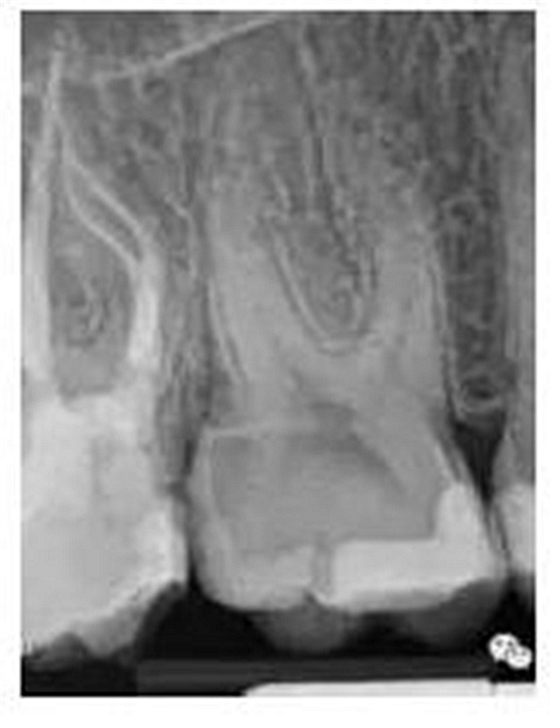

最后來(lái)玩一個(gè)根管治療質(zhì)量的評(píng)估——下圖是武大彭彬教授的一個(gè)病例,仔細(xì)觀察可以挑出一點(diǎn)問(wèn)題,但問(wèn)題事出有因!看看你的“眼力”如何——問(wèn)題在那里?教授的專業(yè)水平是不用懷疑的,那么事出的原因可能是什么?

問(wèn)題答案:這個(gè)病例的問(wèn)題主要反應(yīng)在開(kāi)髓的洞形修整,注意觀察該牙X-RAY的左側(cè)洞壁,如果常規(guī)情況制備成這樣是由于裂鉆破壞了洞壁和洞底所形成的臺(tái)階。如果評(píng)估根管治療的質(zhì)量那是要扣分的!但這個(gè)病例仔細(xì)觀察洞壁形態(tài)就可以看出:該病例屬于再治療的病例,因此還是屬于一個(gè)理想的病例。